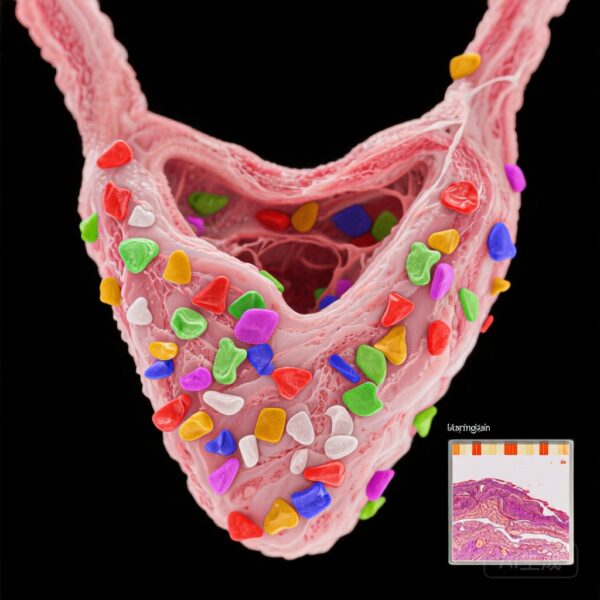

Nghiên cứu này so sánh mô tuyến giáp từ 29 bệnh nhân AIT được xác nhận qua hình ảnh học và 29 đối chứng cùng độ tuổi và giới tính có u tuyến giáp lành tính. MPs được định lượng bằng phương pháp nhiệt phân-gas sắc ký-chromatography-mass spectrometry (Py-GC/MS) và đặc trưng thông qua vi quang phổ Raman và vi kính điện tử quét (SEM).

Tổng nồng độ MPs đáng kể cao hơn ở bệnh nhân AIT (trung vị: 19,9 μg/g so với 1,9 μg/g; p=0,012), với PVC là polyme chiếm ưu thế. Vi quang phổ Raman cho thấy số lượng MPs cao hơn trong mô AIT (172 so với 50,2 đơn vị/g, p=0,037), với kích thước hạt từ 33,9 đến 1467 µm. Đặc điểm hình thái (kích thước, hình dạng, màu sắc) không khác biệt giữa các nhóm.